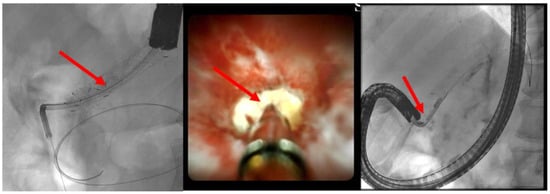

The patient is positioned prone on an X-ray fluoroscopy table and undergoes endoscopic ultrasound (EUS) using a therapeutic longitudinal scanner (e.g., EG 3270 UK, Hitachi Ultraschall, Berlin, Germany; GF-UCT 180, Olympus, Hamburg, Germany; Fuji EG-580UT2, Tokyo, Japan) following unsuccessful conventional ERP, with peri-interventional antibiotic administration i. v. (2 g ceftriaxone or 4 g tazobactam). Once the pancreatic duct is identified, a 19-G needle (Boston Scientific, Ratingen, Germany; Olympus, Hamburg, Germany) is used to puncture it in the direction of the anastomosis or papilla. Pancreatic juice is aspirated and sent for microbiological and cytological examination. Subsequently, the pancreatic duct is visualized via X-ray fluoroscopy following the instillation of the contrast medium (Figure 1 and Figure 2—selected from the clinical picture library of the reporting Dept. of Gastroenterology, Hepatology and General Internal Medicine as all the following figures).

(A) EUS-ERP rendezvous technique: If the wire can be passed through the papilla and the papilla is accessible with the endoscope, a duodenoscope is employed. The guidewire is then grasped with forceps and pulled out, enabling subsequent conventional ERP with endoscopic papillary balloon dilation (EPBD) and stent placement (Figure 3 and Figure 4).

Figure 2. Intraprocedural fluoroscopy (during EUS-guided procedure): Legend see also Figure 1.

Figure 4. After the device change, the wire is grasped with forceps and passed out, followed by a conventional ERP with stent placement (red arrow).

Figure 5. Dilated pancreatic duct (red arrow) in history of necrotizing pancreatitis—suspected DPTS; EUS-guided pancreatography (left panel) with following insertion of a plastic prosthesis (red arrow) for retrograde drainage (middle panel) and endoluminal (endoscopic) control of the right plastic prosthesis position (red arrow—right panel); selected from the clinical picture library of the reporting Dept. of Gastroenterology, Hepatology and General Internal Medicine.